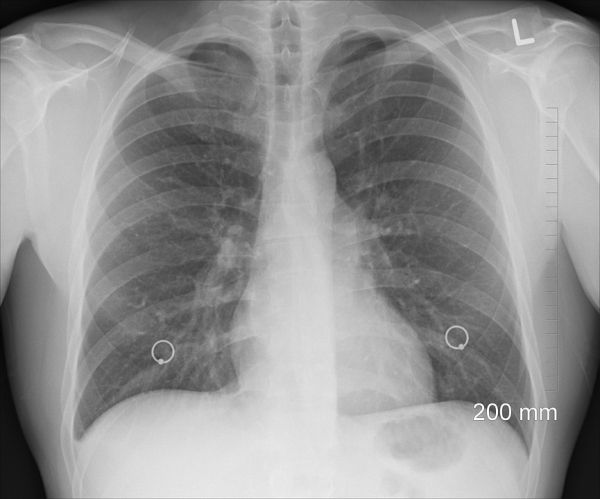

Photo Credit: oracast via Pixabay